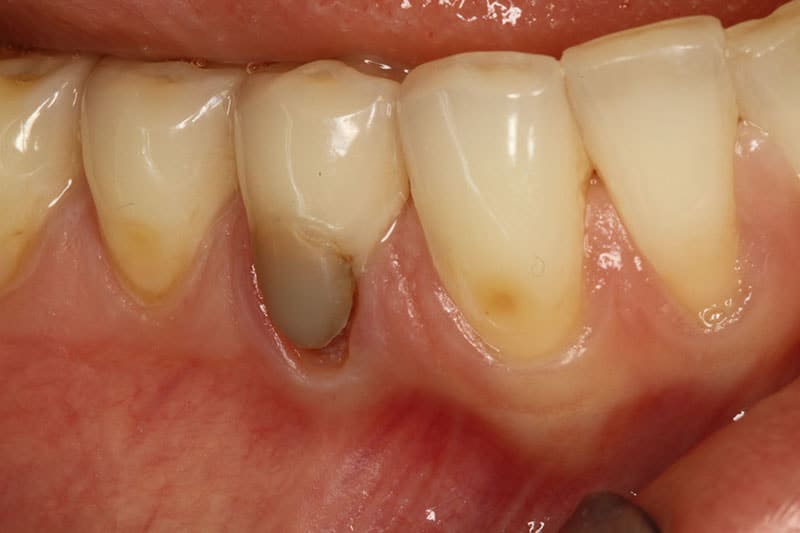

Before treatment Before